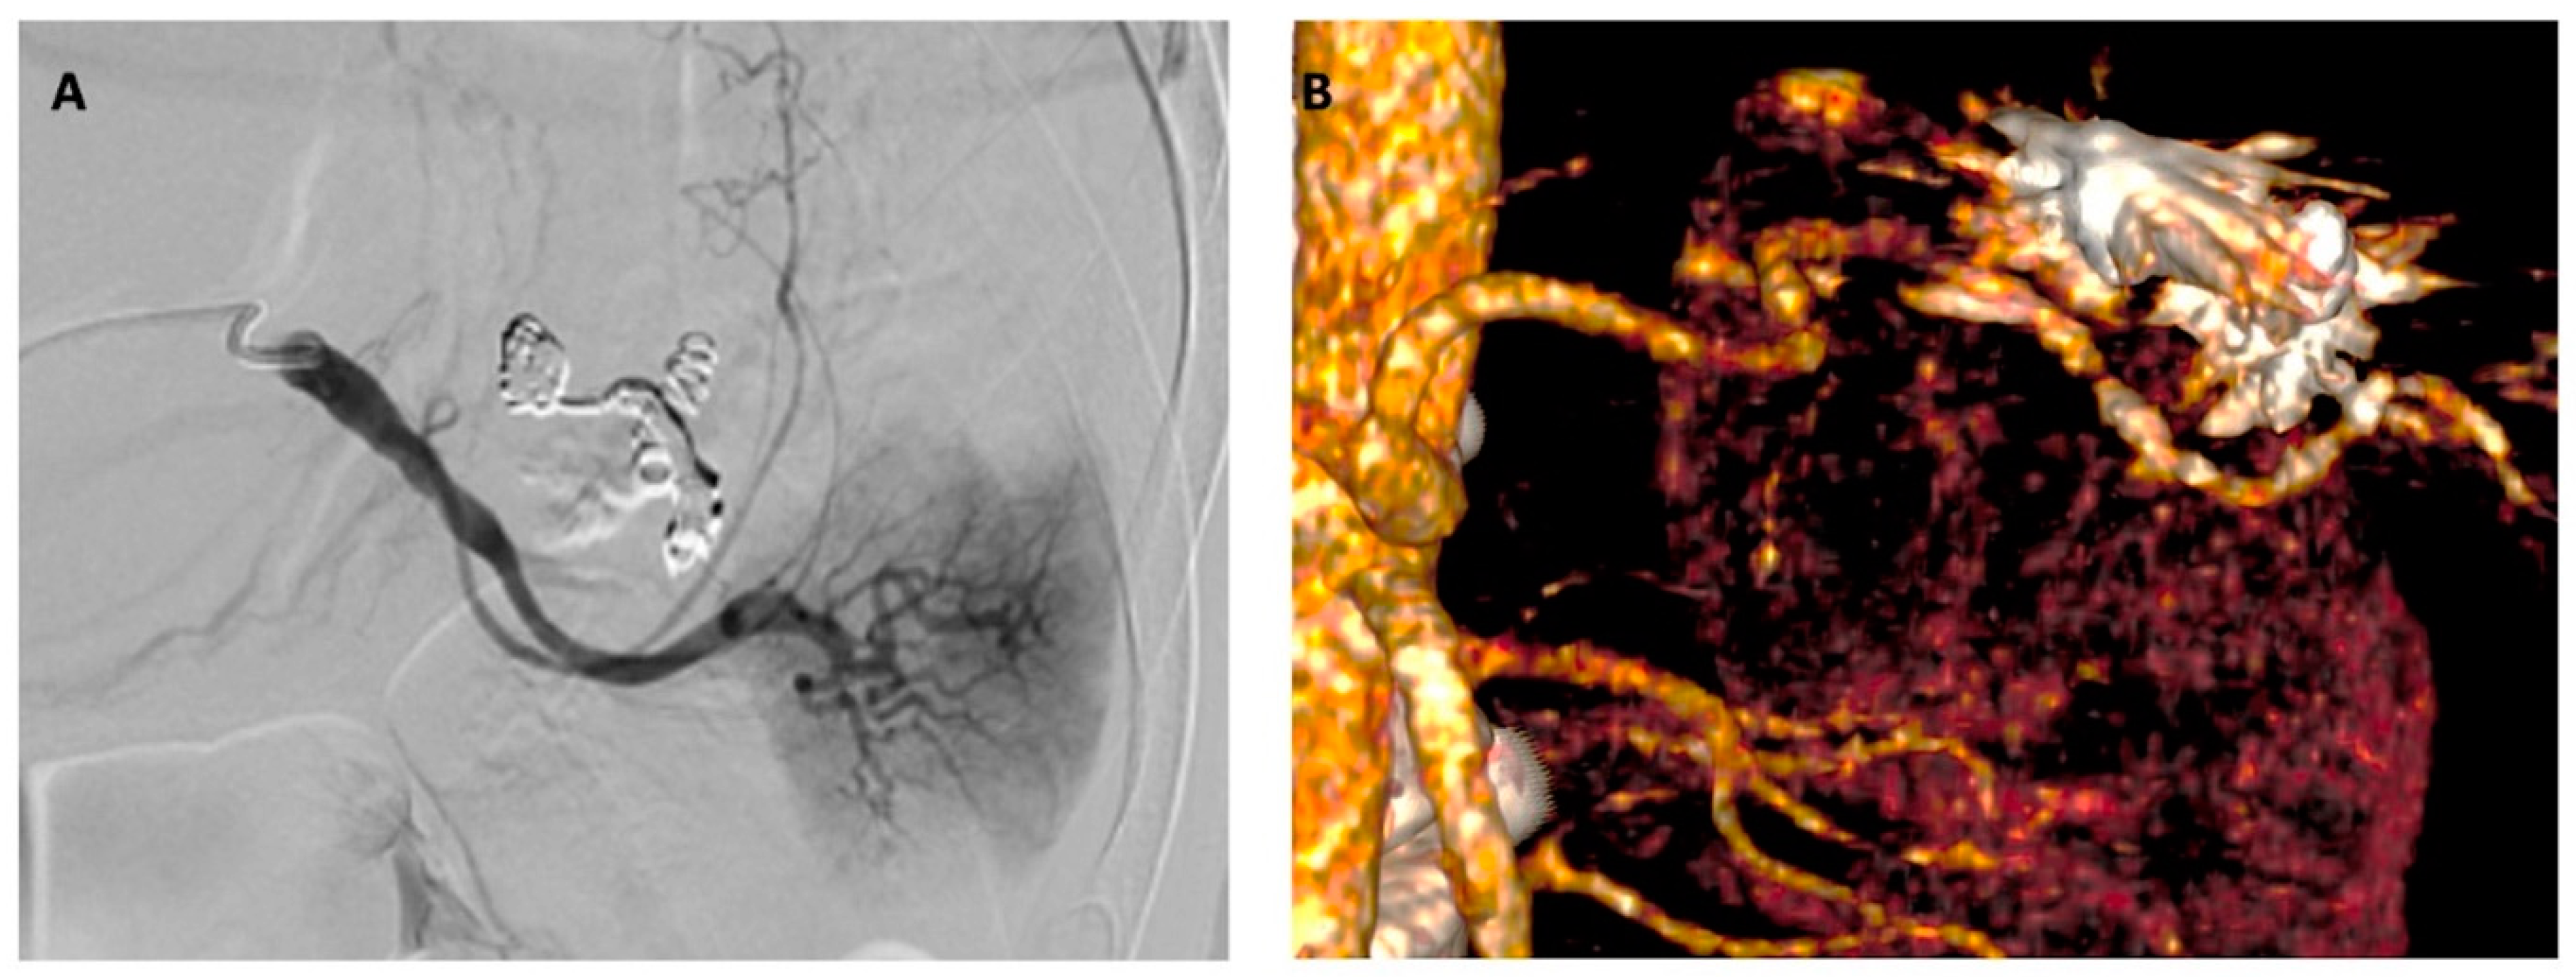

2. Detailed Case Description